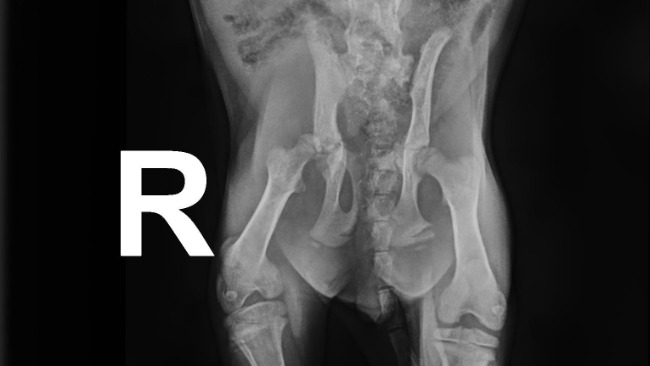

Isię potrącił samochód na kilka dni przed tym, gdy została złapana i przeniesiona z szopy pod Skierniewicami do domu tymczasowego. Prawa kość udowa kotki wypadła ze stawu biodrowego, teraz znajduje się w niewłaściwym miejscu i jak to widać na zdjęciu RTG zahacza o miednicę.

Isia jak przystało na wzorowe kocie dziecię pełni rolę wodzireja rozrabiaki na trzech zdrowych nóżkach, czwartą, chorą się podpiera lub stara się ją podwijać, gdy ta przeszkadza w wybiciu się odrobinę wyżej podłogi. Operacja sprawi, że kotka będzie żyć bez bólu, bez stanów zapalnych biodra, bez zwyrodnień, będzie też sprawnie się poruszać. Aby ten optymistyczny scenariusz się ziścił konieczne będzie obcięcia główki i szyjki prawej kości udowej, chirurg stworzy warunki, aby w okolicy połamanego stawu biodrowego wytworzył się tak zwany staw rzekomy. To on pozwoli małej skakać i fikać koziołki na wszystkie 4 nóżki.